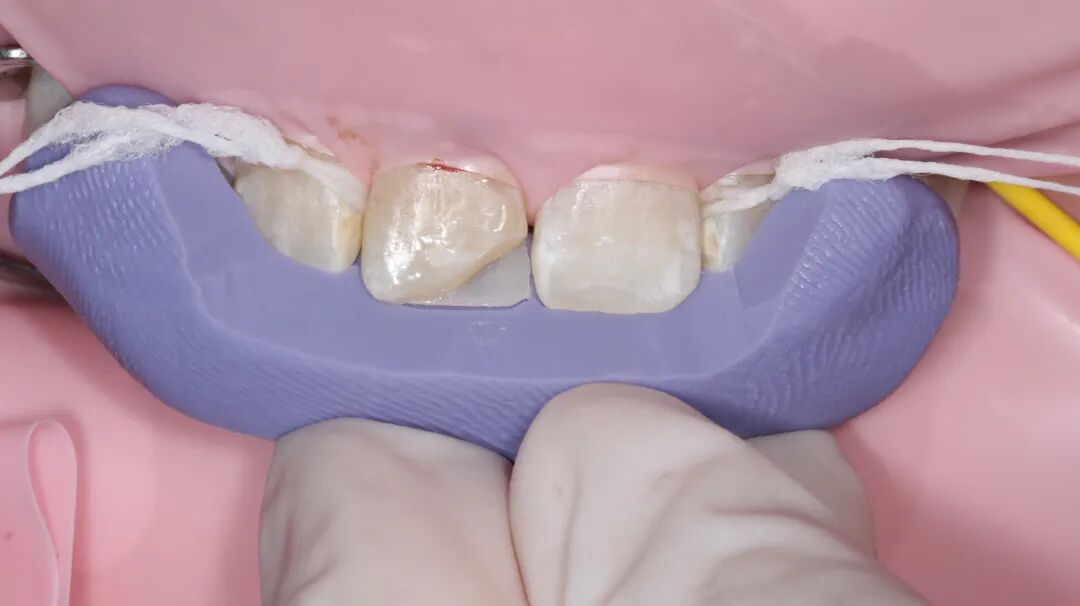

牙医-李子豪【实操病例】

患者女,16岁

主诉:半年前因外伤导致右上1牙体缺损,现暑假期间自觉不美观,今日与家长来我院就诊

检查:口内右上1近中切角折断,患牙不松动,牙髓活力正常。因患者年龄较小,家长不接受冠修复,沟通后选择树脂修复。取术前观测模型,蜡恢复缺损部位,制作硅橡胶导板。橡皮障夹配合【康田正楔线】障下修整缺损面,【康田正消毒刷】涂布自酸蚀粘接剂,放置导板,流体树脂恢复舌侧基本形态,【康田正豆瓣成形片】恢复邻接形态后唇面常规树脂充填,修型,调合,抛光,康田正邻面抛光条抛光邻面。

◆近中切角折断

◆橡皮障夹配合楔线完成上障,障下对折断面打磨后【康田正消毒刷】涂布粘结剂,放置硅橡胶背板,流动树脂恢复折断部位舌侧面为什么牙医不用开口器特邀牙医【实操病例】集锦{9.22}_https://www.jmylbn.com_新闻资讯_第12张